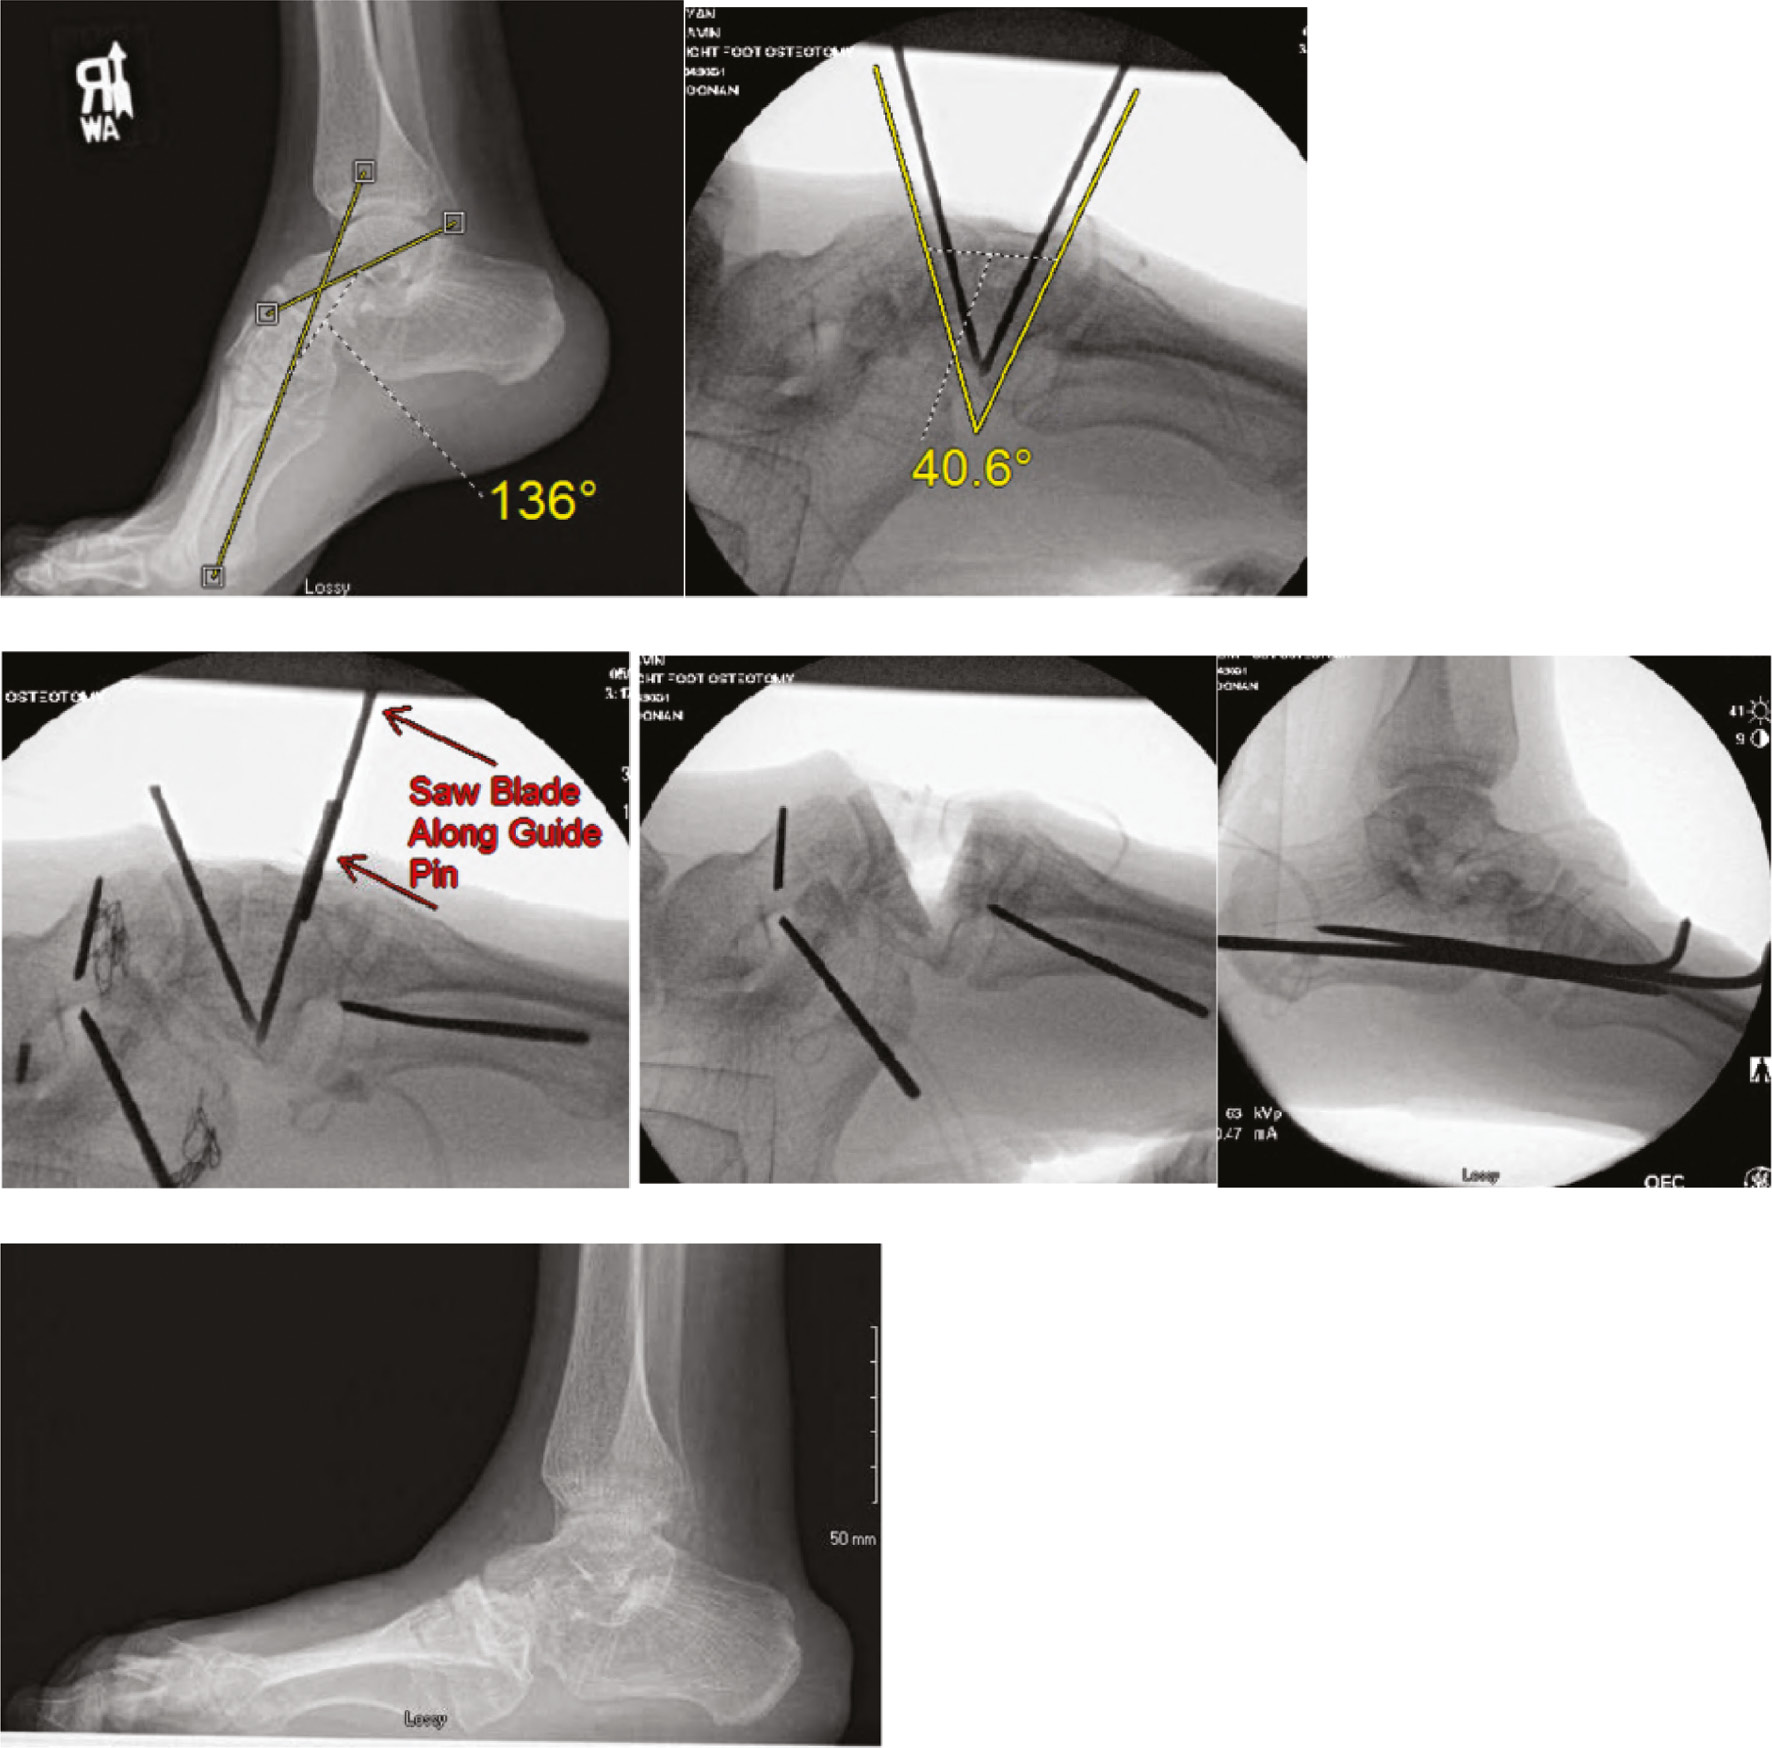

Talonavicular pins can be used in pediatric vertical talus foot deformity or clubfoot surgery for those patients who have failed Ponseti casting. Pin fixation may be used in calcaneal neck lengthening procedures. In older children, larger pins may be used to yield a lateral closing wedge valgus-producing osteotomy in addition to calcaneal neck lengthening. Pins can also be used as guides to precisely orient cuts by using them as intraosseous saw guides.

Pins are utilized to a great degree in foot surgery as a means to effect correction (Figure 17) and to stabilize the foot while it heals.

Figure 17. A 17-year-old boy with arthrogryposis has a fixed cavus deformity of 44 degrees. A midfoot osteotomy was planned and executed by placing two K-wires in the midfoot at 40 degrees to each other. The trajectory of the pins was measured on PACS prior to osteotomy, and the K-wires were cut off in order to act as an interosseus guide for the saw blade. Smooth pins maintained alignment until healed.

In general, smooth pins are used to stabilize opening wedge osteotomies as they can be removed in clinic without sedation. Threaded pins are needed for closing wedge osteotomies as they can keep the bone edges opposed; unfortunately, these need removal in the operating room (Figure 18).

Figure 18. A five-year-old with a history of clubfoot and with residual metatarsus adductus underwent opening wedge osteotomy of the first cuneiform with allograft. A closing wedge cuboid osteotomy was planned with smooth K-wires as interosseus guides and the osteotomy was held closed with threaded K-wires.